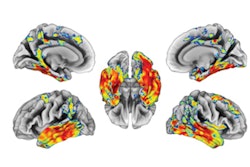

The researchers found C-11 BU99008 uptake was higher in eight beta amyloid-positive patients with cognitive impairment across the whole brain, but particularly in frontal, temporal, medial temporal, and occipital lobes, compared with the control group. Global tracer uptake (mean uptake ± standard deviation) was 82.7 for cognitively impaired subjects and 77.7 in healthy patients.

Statistical parametric mapping analysis of significantly increased C-11 BU99008 uptake as a group for (a) all cognitively impaired (CI) subjects and (b) beta amyloid-positive CI subjects compared with healthy controls, using a cluster threshold of p < 0.05 and with extent threshold of 50 voxels. The color bar indicates the Z-score. Image courtesy of Molecular Psychiatry."This proof-of-concept study provides direct evidence that C-11 BU99008 can measure in vivo astrocyte reactivity in people with late-life cognitive impairment and Alzheimer's disease. Our results confirm that increased astrocyte reactivity is found particularly in cortical regions with high beta-amyloid load," the researchers wrote.